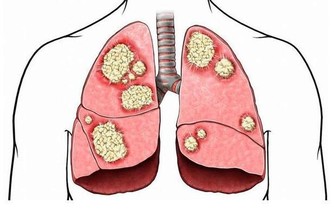

對於高尿酸、痛風患者來說,如果經常無理由的出現口渴,並且大量喝水之後還會感覺到口渴的情況,很有可能就是我們的腎臟毒素積累過多導致的。

因為腎臟需要及時的把這些毒素排出去,但是也需要大量的水分來進行新陳代謝,如果經常出現這樣反常的情況,要注意看一下腎臟是否出現了問題。